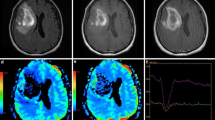

For hematomas associated with neoplasms, the mean VE ratio was 104±15% (mean±standard error; standard deviation 69%; range 7–300%) and the average width of edema 2.4 cm±0.2 cm (standard deviation 0.9 cm) (Figs. 2, 3). The mean VE ratio was 26±2% (standard deviation 12%; range, 5–50%) for hematomas attributed to hypertension or amyloid angiopathy, and 52±10% (standard deviation 42%; range 5–140%) (Figs. 4, 5) for those with vascular malformations. Thus, for non-neoplastic hematomas (spontaneous and vascular malformation groups combined), the mean VE ratio was 37±5% (standard deviation 31%) and average edema width was 0.9±0.1 cm (standard deviation 0.5 cm). Both the VE ratio ( P =0.009) and the width of the zone of vasogenic edema ( P =0.0001) were significantly greater for neoplasm-associated hematomas.

A 14-year-old child with coagulopathy and right inferior parietal lobar hematoma. a Axial T1-weighted spin-echo image shows a high-signal mass ( open arrow) consistent with a subacute lobar hematoma. b On a fast spin-echo T2-weighted image, the mean diameter of the hematoma is 2.3 cm and the width of vasogenic edema ( between arrows) is 3.2 cm; the VE ratio is 139%. Biopsy showed metastatic osteosarcoma

A 6-year-old child with an acute right pontine hematoma. a CT shows dense hemorrhage ( arrow) in the right side of the pons. b Fast spin-echo T2-weighted image 2 days later shows an enlarging hematoma ( open arrow) that measuring 2.9 cm in average diameter. The maximum width of asymmetric high signal around it 2.9 cm ( between small white arrows); the VE ratio is thus 100%. Biopsy revealed a glioma